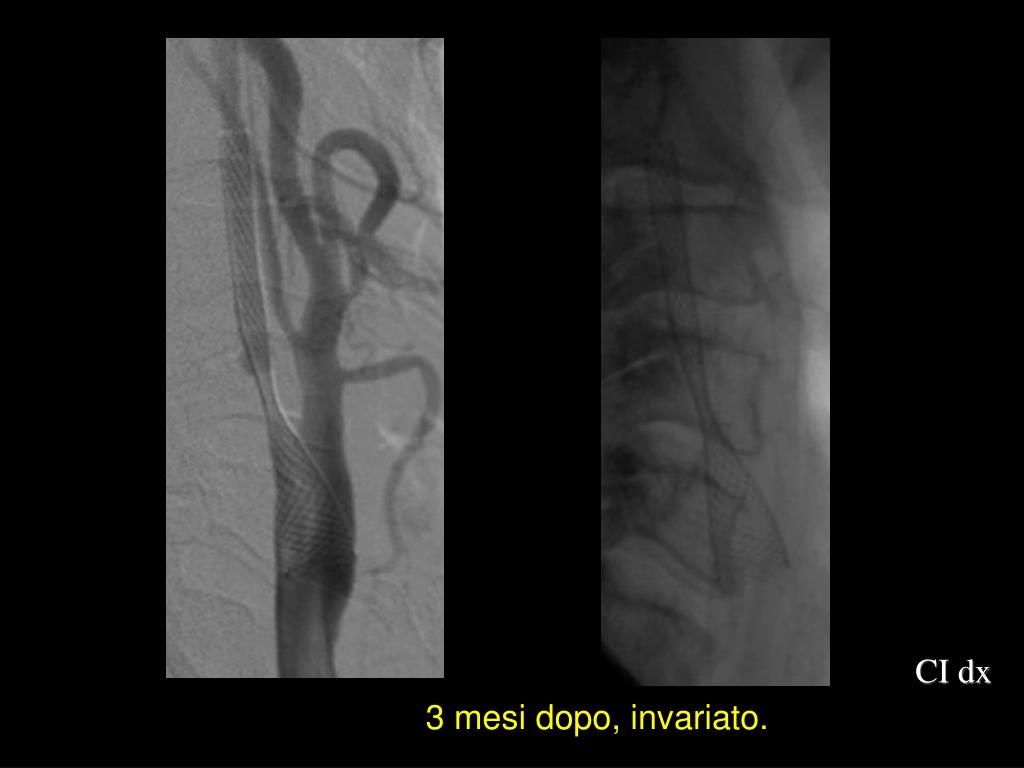

29. CI dx 3 mesi dopo, invariato.

30. Carotide interna sinistra, 2° stent (3 mesi dopo il 1°)

31. 3 mesi dopo il 2° stent

36. Controllo dopo 7 mesi 3 mesi